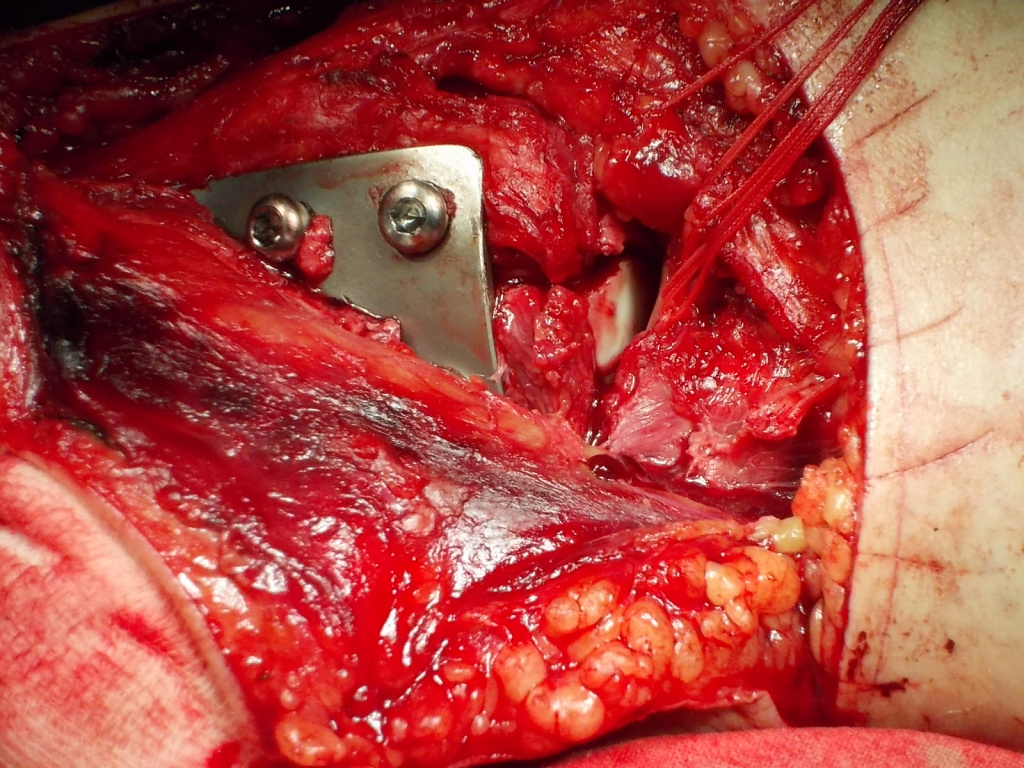

Использование материала Остеоматрикс при импрессионном оскольчатом переломе наружного мыщелка большеберцовой кости по типу Schatzker II

Использование материала Остеоматрикс при импрессионном оскольчатом переломе наружного мыщелка большеберцовой кости по типу Schatzker II.

Операция - открытая репозиция, остеосинтез большеберцовой кости опорной пластиной с костной ксенопластикой маетриалом "Остеоматрикс". На контрольных снимках в три и шесть месяцев имеется консолидация перелома, миграции фиксатора нет, имеется остеоинтеграция ксенопластического материала. Функция коленного сустава полная.